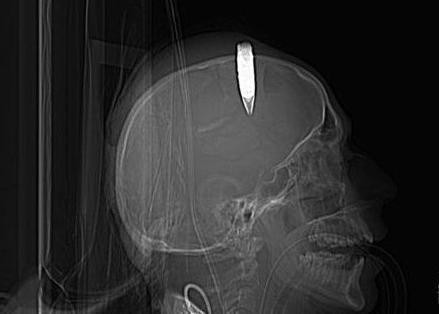

一名士兵的头部嵌入子弹的X光片

据《世界报》12月29日报道,俄罗斯一名退休工程师被认为是个医学上的奇迹。他82年前头部遭枪击,子弹留在了脑袋里,但他安然无恙,生活也没受到任何影响。

《新英格兰医学期刊》报道称,在该男子3岁时,他的哥哥玩耍时不小心开枪击中了他的头部。随后,他晕厥了长达数小时,但后来没经过任何治疗就痊愈了。长大后,该男子还成为了出色的工程师。

这颗嵌在他脑袋里的子弹几乎将陪伴这名85岁的男子一生,但他的健康却几乎没受到任何影响。